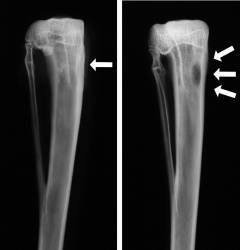

Рентгенография

Наиболее эффективным методом диагностики остеомиелита является рентгенография. Снимки пораженной кости выполняются в двух проекциях, что позволяет точно определить локализацию и степень костного некроза. Первые признаки воспаления у детей могут проявляться на 3-5 день болезни, у взрослых — на 12-15 день. Рекомендуется проводить рентген в день поступления для контроля динамики воспаления.

Рентгенологические признаки остеомиелита:

- исчезновение границы между губчатым и компактным веществом с второй недели;

- очаги костного разрушения и разряжения (остеопороз) круглой или овальной формы;

- утолщение и изменение рельефа надкостницы;

- секвестры различной формы и размера, выявляемые в конце первого месяца.

К 3-4 неделе признаки становятся более выраженными. Гнойные полости увеличиваются и сливаются. Периостальная реакция охватывает здоровую надкостницу. При распространении гноя в суставе увеличивается суставная щель и изменяются формы суставных поверхностей, что приводит к образованию остеофитов.